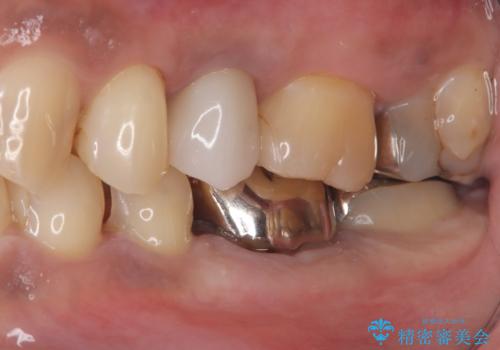

- 主訴:銀の詰め物が何本か入っているので白くしていきたい

保険適用のメタルインレーのやり替え希望だったため、審美性・適合性の良いセラミックインレーでのやり替えとなりました。

メタルインレーを除去したところ、二次カリエスうを確認したため除去・CR裏層の後、形成・印象しています。